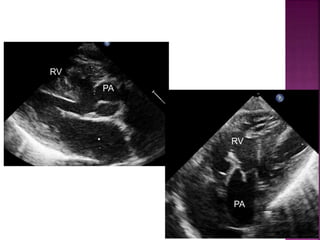

subpulmonary VSD

• size in relation to the diameter of the pulmonary artery

• presence and severity of a subpulmonary obstruction

• subcostal coronal and parasternal long axis planes

RV

PA

Guideline DORV